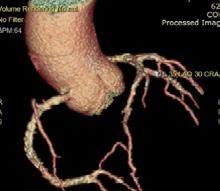

Figura 1. Pacient de 57ani cu simptomatologie acută sugestivă pentru AVC ischemic acut: CT -ul nativ nu a decelat elemente de semiologie sugestive pentru AVC ischemic acut (A), însă secvențele IRM au evidențiat o arie în hipersemnal FLAIR (B) și cu restricție de difuzie (C) localizată occipital paramedian dreapta, sugestivă pentru AVC ischemic acut (Spitalul Clinic de Urgență „Prof. N. Oblu“, Iași)

În contrast, imagistica prin rezonanță magnetică, în special secvențele de difuzie, oferă o sensibilitate superioară pentru detectarea precoce a infarctului ischemic,

fiind capabilă să identifice modificări la nivel celular la doar câteva minute după debutul simptomelor (Figura 1) (Mouridsen et al., 2020), (Nukovic et al., 2023). De asemenea, IRM este capabilă să ofere o evaluare superioară a integrității parenchimului cerebral, a viabilității țesutului și a extinderii leziunii ischemice, facilitând o caracterizare mai detaliată a AVC-ului ischemic (Cortés-Albornoz et al., 2025).